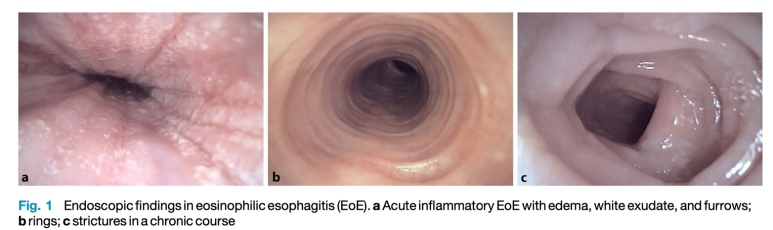

(왼쪽) 내시경소견, (오른쪽) 조직검사소견증상에서 하나씩 살펴보겠습니다.유럽 가이드라인에서는 소아와 성인의 증상을 나누어 설명을 하고 있었습니다. 소아의 경우 역류가 주된 증상으로 구토, 복통, 식사 거부 등의 증상이 있으며 성인의 경우 고형물 섭취가 어렵고 흉통이 일어나는 것으로 알려져 있습니다.

미란성 식도염의 경우 붉은 발적과 발적병변 주변에 부종 소견이 있는 반면 호산구 식도염의 경우 Furrow와 ring이 특징적인 소견입니다.

주의할 점은 내시경 소견으로 호산구 식도염을 진단해서는 안 된다는 것입니다. 예를 들면, EREFS 시스템이라는 것이 있습니다. 이 점수체계는 호산구 식도염 내시경 소견의 중증도를 점수화하여 기술하는 기준입니다. 중요한 것은 이 점수가 높다고 해서 호산구 식도염의 disease activity가 높다고 이야기하거나 관해됐다는 것을 말할 수 없다는 것입니다.